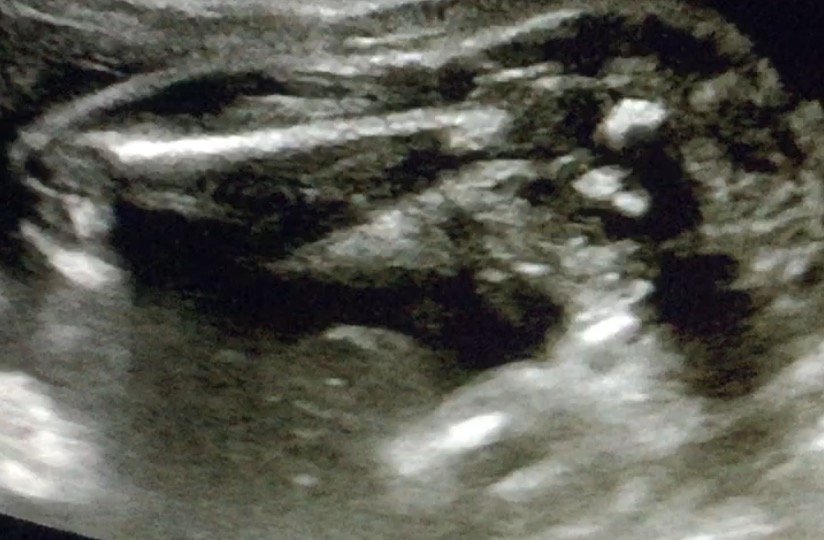

Can anyone tell me what gender they see?

Thankyou Not sure if I'm seeing something that resembles a hamburger between the legs, maybe I'm seeing things

My guess would be girl but I'm not 100% xx

Can anyone else give their opinion, I managed to get a screen shot from a super quick video, the top photo is mine and the bottom is a confirmed girl showing the labia. Can anyone see a similarity with these 2?

Still thinking girl, I take it that is a potty shot? Definitely looks like 3 girly lines x